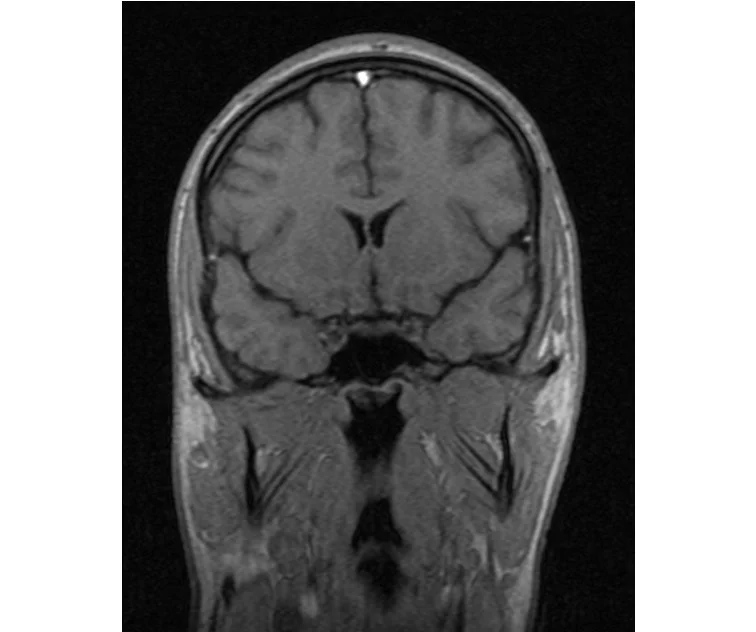

делал в обласной на siemense.В заключении выданом мне через 15мин.после мрт (легкая дегидрация)

Меня смутил факт выдачи заключения через 10мин(наверно они у них зарание напечатаные)я не медик.достаточно мимолётного взгляда на снимки?А вы видете на них гидроцефалию? Я лиш спросил куда идти с результатами томографии?и не хотел никого роздражать.

Я попросил взглянуть на снимки и сказать видна.ли на них гидроцефалия?или куда обратится за консультацией по этому вопросу?В мрт снимках наверно розбирается любой нервопатолог(я так предположил)

Я уже говорил, что независимо от того, есть на МРТ гидроцефалия или нет, лечиться тебе нужно только в том случае, если есть какие-либо проявления болезни, иначе на все эти анализы можешь забить... Но давай все-таки разберемся с томограммой.

Итак, с самого начала томограмма обозначала срез какого-либо органа на определенной глубине, позволяла заглянуть вовнутрь. При компьютерной томографии аппарат делает десятки срезов головного мозга в разных направлениях и из этого множества срезов он моделирует полноценное объемное изображение мозга в натуральную величину. Обрати внимание, компьютер работает не с этими миниатюрными изображениями, а с трехмерной моделью в масштабе 1:1. Эту модель вдоль и поперек анализирует суперсовременный компьютер, выполняющий миллионы операций в секунду. Только ***** может пытаться перепроверить компьютер, ведь человеку не хватит всей жизни чтобы проанализировать то, что компьютер с тобой сделал за 10 минут. Я хочу, чтобы ты это понял!

Ты разместл здесь несколько миниатюр и хочешь, чтобы врач по ним создал полноценное объемное изображение в натуральную величину, а потом осмотрел его со всех сторон и дал заключение? Но ведь это невозможно. Это просто насмешка над врачом, это издевательство над здравым смыслом. Принеси Букеру уменьшенный в 50 раз снимок зуба и спроси у него, в каком состоянии там корневые каналы. Или давай я дам тебе скрин со спутниковой карты города и попрошу тебя описать, какого цвета и какой модели запечатленная со спутника машина, какой у нее гос.номер, сколько в ней пассажиров, сколько из них мужчин и сколько женщин...